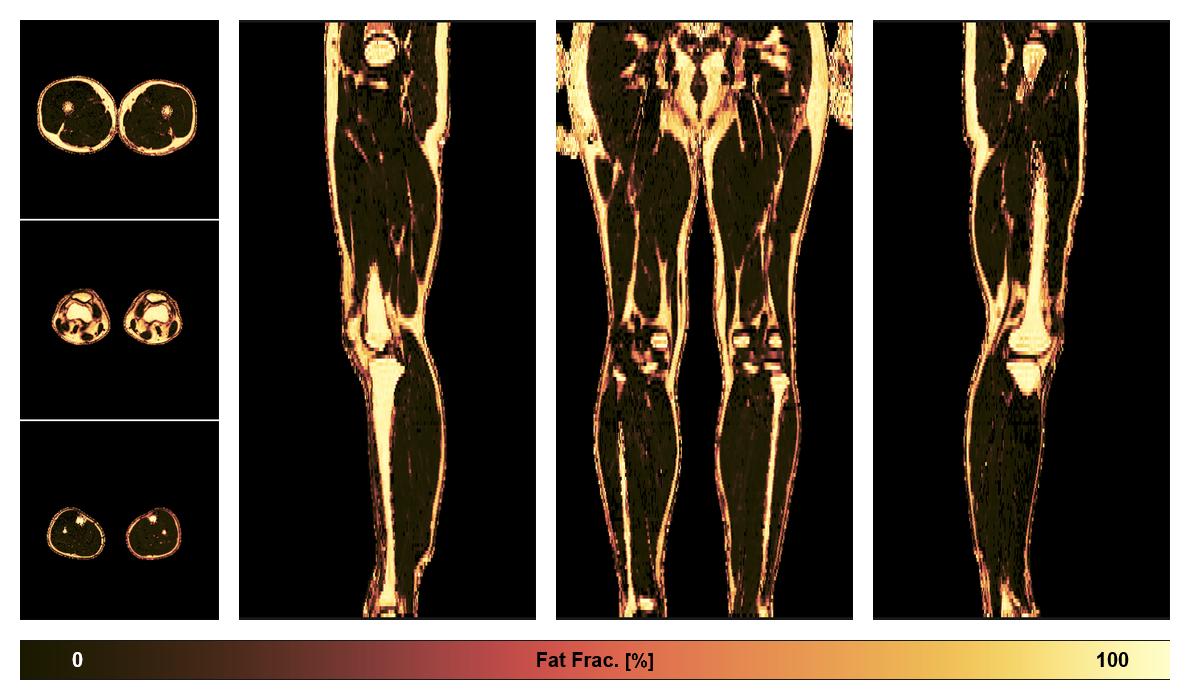

• Fat fraction

The fat fraction of the lower extremity obtained from the dixon reconstruction for muscle water fat quantification.